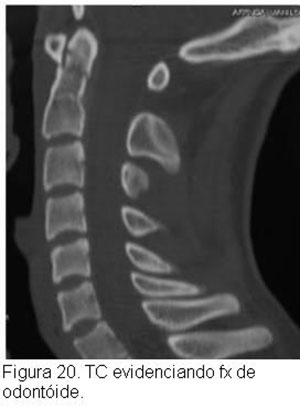

No estudo radiográfico, nas fraturas sem desvio, seja na projeção ântero-posterior, seja na de perfil, apenas se verá o traço de fratura do dente do áxis, e nas fraturas com desvio será vista a fratura com desvio do fragmento distal e o escorregamento do atlas. Nas fraturas sem desvio por vezes é muito difícil que se veja o traço de fratura, só sendo possível o diagnóstico pela tomografia.

Ainda quanto ao diagnóstico radiológico das fraturas sem desvio deve-se acrescentar que carece haver cuidado especial com as crianças, quando ainda não ocorreu ossificação completa da vértebra.Radiologicamente, na criança, o dente e o corpo do áxis estão separados por uma faixa de tecido transparente ao raio X, que progressivamente vai estreitando, até desaparecer aos 10-11 anos, quando o dente e o corpo do áxis se fundem, o que raramente não se completa em idades maiores. A não fusão do dente do áxis pode simular uma fratura sem desvio. Os pacientes com fratura do dente do áxis freqüentemente têm queixas pobres, apenas de cervicalgia pouco intensa e certa dificuldade para a movimentação do pescoço, não raramente procurando tratamento vários dias depois do acidente. Algumas vezes procuram tratamento referindo dor violenta, grande dificuldade à movimentação e suportando a cabeça com as mãos. Sinais neurológicos só aparecem numa pequena minoria (Figuras 18,19 e 20).